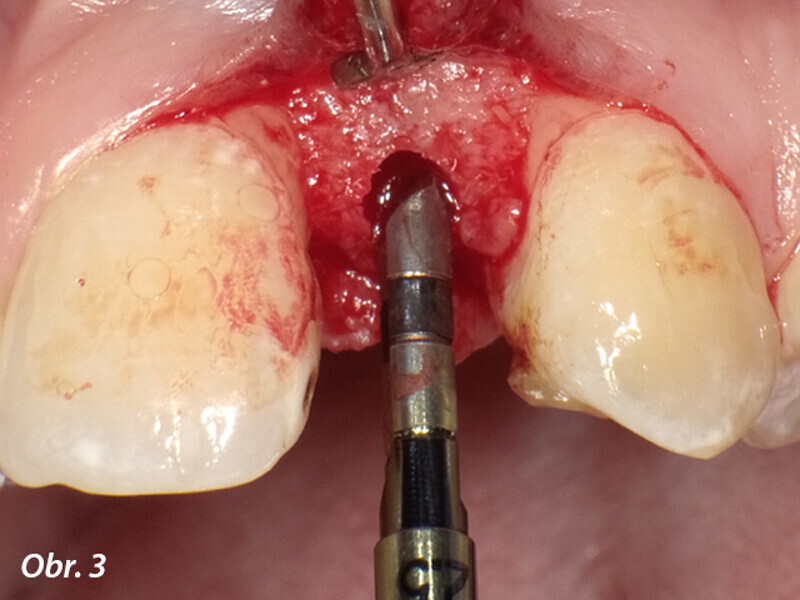

Aproximální rozšíření mezi kořeny zubů za účelem zavedení úzkého implantátu